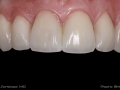

As Facetas Cerâmicas (lentes de contacto dentárias ou laminados), permitem corrigir da maneira mais estética e conservadora possível, problemas de forma e tamanho, côr e posição dos dentes, bem como substituir restaurações antigas e inestéticas.

São aderidas químicamente ao esmalte dentário de uma forma permanente, com o objectivo de melhorar a estética dos nossos pacientes.